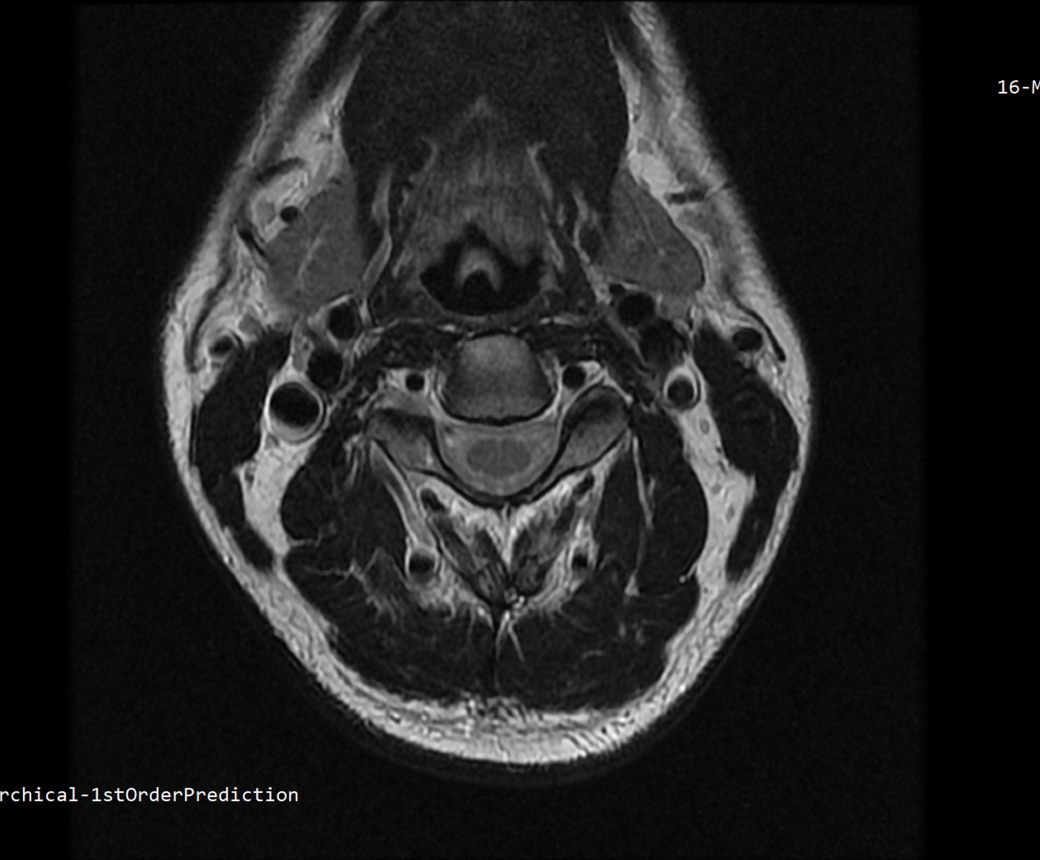

안녕하세요 목 경추 상단부터 순서대로 mri 촬영인데요

전체적으로 봐주시면 감사하겠습니다

• 3번 째 사진